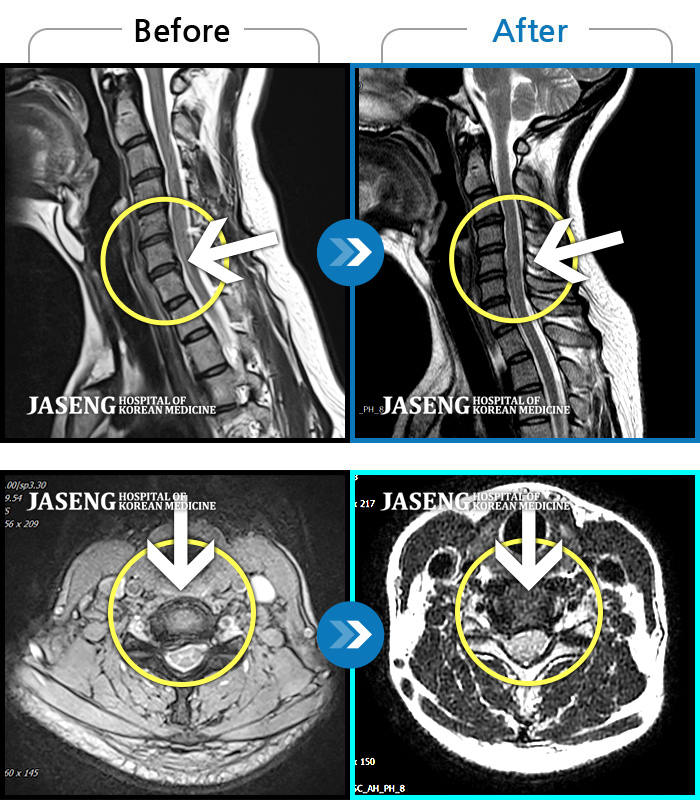

양측 목, 어깨, 팔에 찌릿한 통증으로 일상생활에 지장이 있었습니다.

2020.08.14 ~ 2025.07.02

Before

After

목과 등이 찌르듯이 날카롭게 아프다.

2023.03.15 ~ 2025.05.31

좌측 목, 어깨, 상지 찌릿한 방사통으로 일상생활 지장, 야간통이 심하다

2023.06.09 ~ 2025.03.10